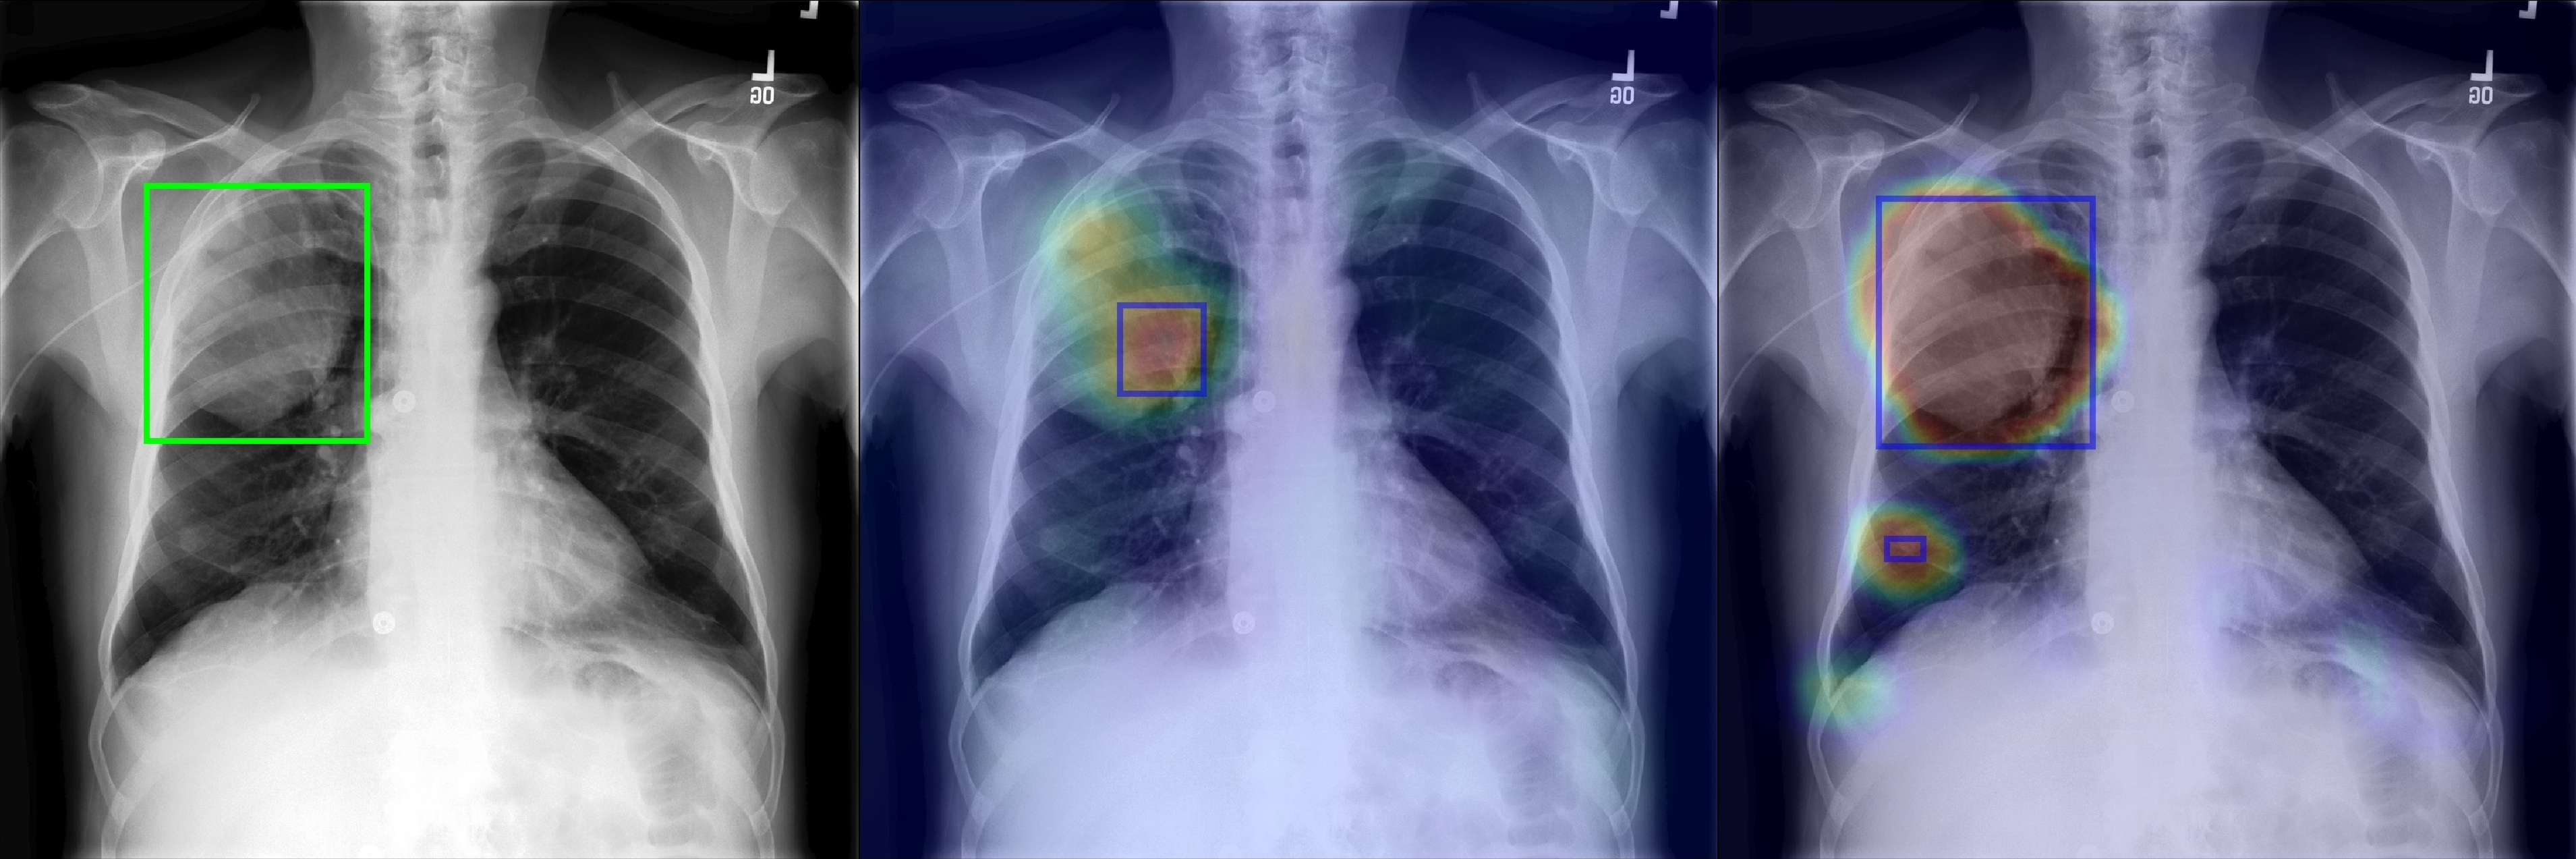

Figure 2 shows a few selected examples of the probability maps generated by PCAM pooling and the class activation maps generated by LSE pooling together with the predicted bounding boxes. Compared to the class activation maps, the probability maps are visually more clear with sharp boundaries around lesion regions. We attribute the improved visual quality to the probabilistic interpretation of the sigmoid-bounded class activation map and explicitly using it for training with global pooling.

We notice the probability maps generated by PCAM pooling tend to enlarge regions of interest in general than class activation maps from LSE pooling, especially when the ground truth regions are small, such as “Nodule” in Figure 2. This may explain the fact that PCAM pooling has relatively larger average false positives than CAM with LSE pooling.

(a) Atelectasis

Figure 2: Selected samples of localization heatmaps and their bounding boxes generated by LSE pooling and PCAM pooling on the test set of ChestX-ray14 [7]. In each subfigure, the left panel is the original chest X-ray with the ground truth bounding boxes (green), the middle panel is the class activation map and predicted bounding boxes (blue) by LSE pooling, the right panel is the probability map and predicted bounding boxes (blue) by PCAM pooling.